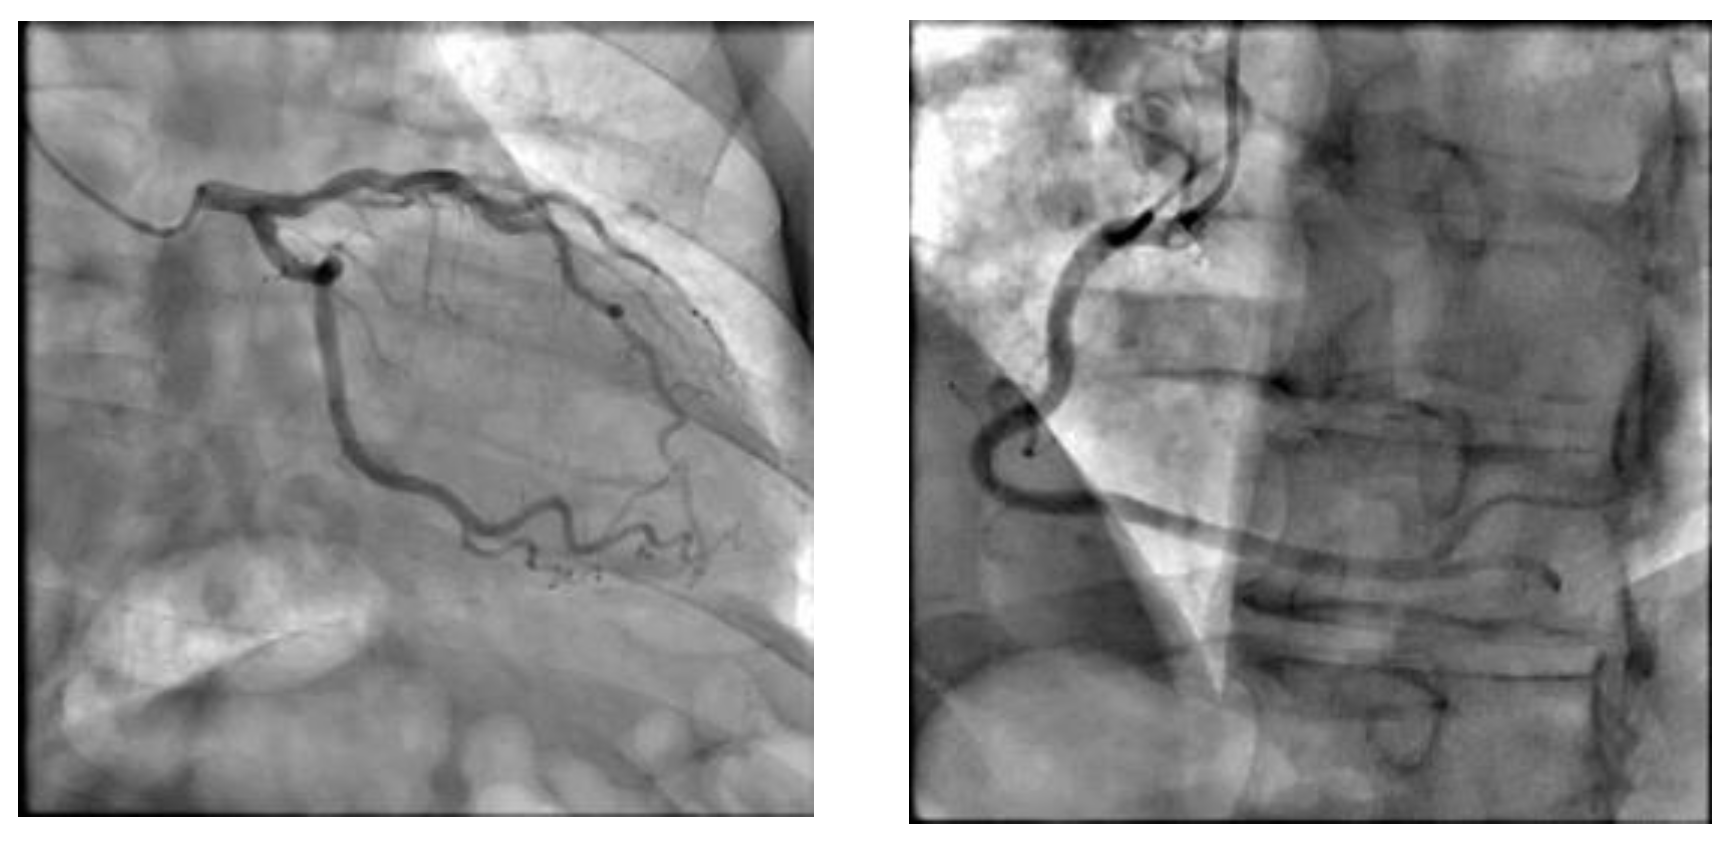

10.3. Coronary Angiography

| 38 | Chest pain | 44 | Reverse | CA | No | 3 | Both positive | Good | Alive w/o complications |

| 40 | Dyspnea | 43 | Reverse | CA | No | 3 | Both positive | Good | Alive w/o complications |

| 37 | Dyspnea | 34 | Apical | CA | No | 4 | Both positive | Good | Alive w/o complications |